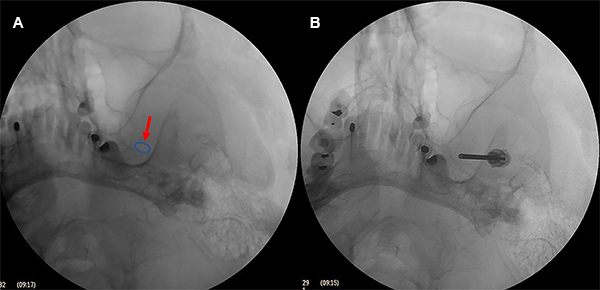

El balón con una jeringa de insulina previamente cargada con contraste radiológico (Iopamidol 612,4 mg /ml) fue lentamente insuflado usualmente entre 0.5 a 1 ml hasta obtener un balón en forma de pera (Figura 7A), o en reloj de arena en tamaño completo (Figura 7B). Se mantuvo insuflado por 60 segundos.

Figura 7:

Formas de balón. (A) Pera, (B) Reloj de arena, (C) Oval.

Figura 8:

La forma de pera indica que la punta del balón se encuentra dentro del poro trigeminal, que es donde debe estar para comprimir el nervio trigémino adecuadamente. Esta forma de pera correspondería a la anatomía interna de la cavum de Meckel y es indicador que está comenzando a sobresalir del cavum de Meckel hacia el poro trigeminal.

La forma de reloj de arena corresponde cuando la punta del catéter a atravesado parcialmente el poro trigeminal hacia la fosa posterior y el balón se infla parte dentro del cavum de Meckel y parte dentro de la fosa posterior. El término reloj de arena se asigna a formas en las que se identificó un istmo con un diámetro menor entre 2 partes redondas del balón con un diámetro mayor.

Cuando el balón es de forma oval (Figura 7C), redonda, elíptica o irregular, se desinfló el balón y la aguja fue retirada y reposicionada, inclusive se puede cambiar de catéter Fogarty hasta lograr la forma de pera o de reloj de arena, en caso de no ser posible por lo menos se debe lograr la forma oval. En estos casos generalmente se terminó insuflando entre 1.5 a 3 minutos.

La forma oval o redonda pueden aparecer debido a un cavum de Meckel grande, poca cantidad de contraste o una posición incorrecta de la punta del catéter. En la forma elíptica, el catéter está fuera del cavum de Meckel, en posición lateral infratemporal.